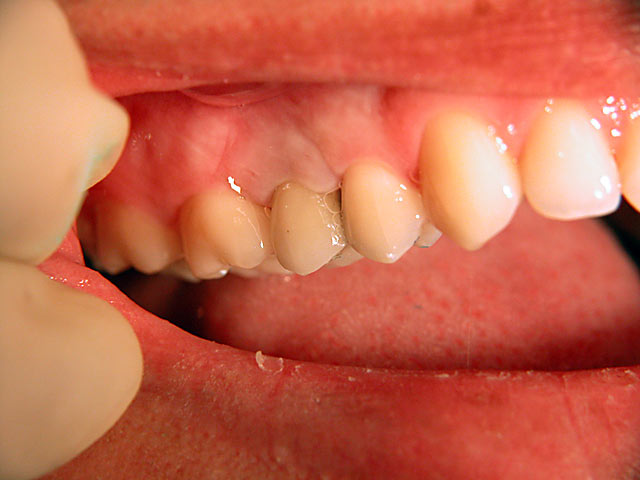

Die folgenden Patientenfälle sollen Ihnen einen Einblick in die Möglichkeiten der modernen Implantation geben.

Implantation mit Knochenblock-Implantaten: